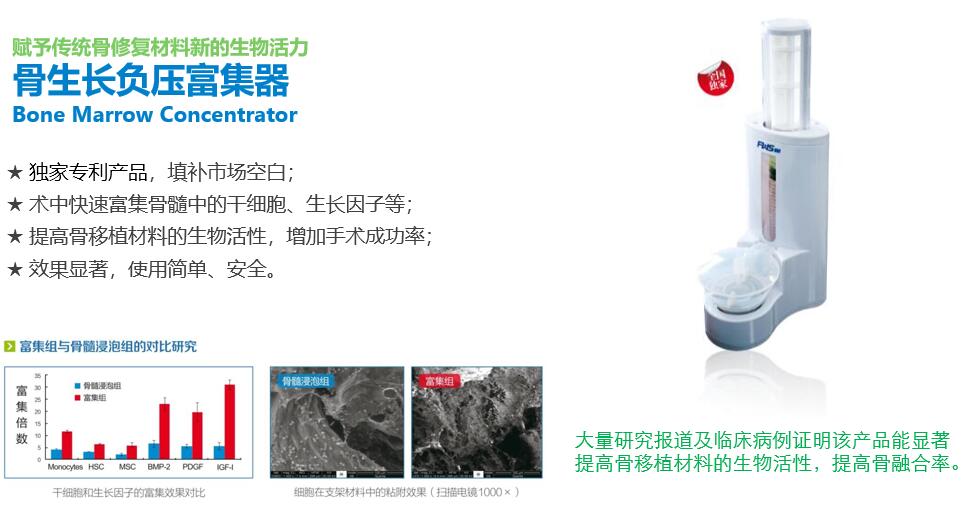

骨生長負壓富集器彩頁

發布時間:2020-01-07

骨生長負壓富集器SCI論文7篇

發布時間:2019-11-07

骨生長負壓富集器SCI論文(中文摘要)

發布時間:2019-11-07